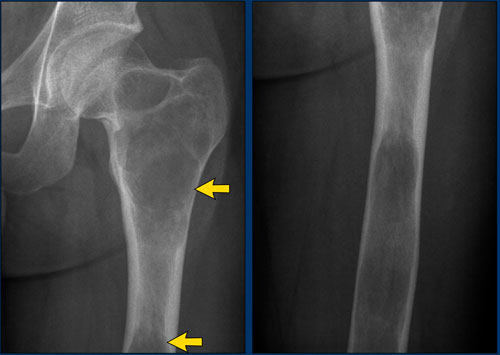

Benign periosteal reaction

Detecting a benign periosteal reaction may be very helpful, since malignant lesions never cause a benign periosteal reaction.

A benign type of periosteal reaction is a thick, wavy and uniform callus formation resulting from chronic irritation.

In the case of benign, slowly growing lesions, the periosteum has time to lay down thick new bone and remodel it into a more normal-appearing cortex.

Image

Benign periosteal reaction in an osteoid osteoma.

Large arrow indicates solid periosteal reaction.

Small arrow indicates nidus.